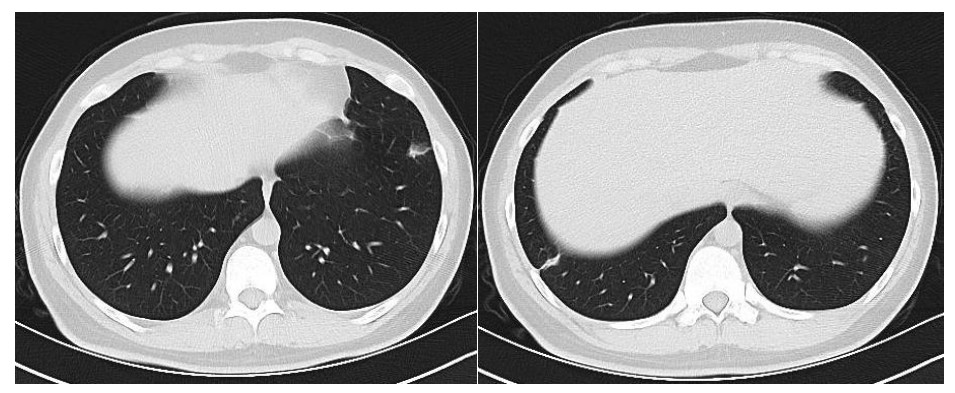

患者男性,21岁,主因“间断发热、寒战伴头晕头痛2周”于2021年11月18日急诊收入院。患者诉2周前进食烧烤后出现发热,体温最高可达42℃, 伴畏寒、寒战、咽痛、头晕、头痛、乏力,就诊于本院耳鼻喉科后,查体见扁桃体有脓点,快测降钙素原(procalcitonin,PCT)为37.27 ng/mL,胸部CT检查未见异常,考虑诊断为“急性化脓性扁桃体炎”,先后给予左氧氟沙星、阿奇霉素抗感染及甲泼尼龙控制炎症后上述症状未见明显好转,为进一步治疗,收入急诊病房治疗,既往体健,入院时查体:体温41℃,脉搏98次/min,呼吸频率23次/min,血压120/60 mmHg(1 mmHg=0.133 kPa),患者神志清楚,急性病容,精神较差,颈部浅表淋巴结触及肿大,右侧较大约2.0 cm ×0.5 cm,左侧较大约1.3 cm×0.7 cm,质软,活动度好,界限清楚,有压痛,表面皮肤无红肿,无破溃,双肺呼吸音清,未闻及干湿性啰音,心脏听诊无杂音,腹软,无压痛及反跳痛,双下肢无水肿。血常规检查白细胞计数10.49×109/L, 中性粒细胞百分比94.6%,血红蛋白120 g/L, 血小板计数107×109/L,PCT 42.83 ng/mL,白介素6(interleukin, IL-6)980.30 pg/mL,C反应蛋白211 mg/L,G试验、GM试验阴性。胸部CT检查示右肺上叶可见一单发实变影,其内可见空洞(图 1)。根据病史、查体和辅助检查考虑诊断为肺脓肿,给予注射用哌拉西林钠他唑巴坦4.5 g Q8h治疗,入院第2天,患者仍有发热,体温最高38.7℃,给予对症处理,入院第3天患者体温峰值有所下降,体温维持在37~38℃,考虑抗炎有效,痰培养结果回报为纹带棒杆菌,草绿色链球菌(奈瑟菌属),考虑这2种细菌为皮肤或口腔的正常菌群,为条件致病菌,该细菌导致发热的可能性较小,继续给予哌拉西林钠他唑巴坦治疗。入院第5天血培养回报血液中找到坏死梭杆菌,考虑为血流感染。加用甲硝唑1 g每8 h一次抗感染治疗,复查血常规白细胞计数8.14×109/L, 中性粒细胞百分比81.5%,血红蛋白120 g/L, 血小板计数246×109/L,PCT 3.43 ng/mL,IL-6 13.04 pg/mL,C反应蛋白5 mg/L,炎性指标较前明显下降,考虑抗炎治疗有效,继续目前抗生素治疗。入院第10天患者体温仍有低热,体温36.5~37.5 ℃,复查胸部CT见双肺多发小结节,双肺多发空洞病变,考虑炎性可能(图 2)。颈静脉超声检查提示患者左侧颈内静脉血栓形成,给予依诺肝素0.4 mL每12 h一次抗凝治疗,根据血培养结果、胸部CT表现和颈静脉超声结果,考虑该患者诊断为坏死梭杆菌导致Lemierre综合征(Lemierre syndrome, LS)。用哌拉西林钠他唑巴坦联合甲硝唑治疗后仍有低热,化验检查PCT为0.30 ng/mL,IL-6为3.52 pg/mL,C反应蛋白为3 mg/L,胸部CT示肺部空洞较前增加,考虑感染未完全控制,改为调整抗生素为比阿培南0.6 g每12 h一次联合甲硝唑1g每8 h一次抗感染治疗,治疗1周后患者体温恢复正常,CT检查示双肺多发空洞消失,残留少量索条影(图 3),患者病情好转出院,出院带药给予口服甲硝唑联合阿莫西林抗感染治疗,利伐沙班抗凝治疗,随诊2周后复查胸部CT正常。

| 右肺上叶可见一单发实变影,其内可见空洞 图 1 入院时胸部CT |

LS的致病菌主要为坏死梭杆菌,因此LS也被称为坏死梭杆菌病,其他致病菌包括核杆菌、类杆菌、链球菌和葡萄球菌等[5]。坏死梭杆菌为厌氧革兰阴性多形态杆菌,广泛存在于人类和动物的口腔、上呼吸道、胃肠道和泌尿生殖道的正常菌群。坏死梭杆菌可以产生白细胞毒素、内毒素、溶血素和血细胞凝集素等,白细胞毒素和溶血素与脓肿形成相关,血细胞血凝素可引起动静脉血栓形成,可导致转移性脓肿,弥漫性血管内凝血和血小板减少也与此有关[6]。患者起初为咽部感染,然后通过咽旁间隙侵袭至颈内静脉,形成颈内静脉血栓,脓毒性栓子随着血流播散至肺部,引起肺部脓肿和肺栓塞。本例患者刚发热时胸部CT正常,门诊给予喹诺酮类药物和大环内酯类药物治疗2周后,入院时胸部CT示患者右肺中叶单发实变影,其内可见空洞样变,后随病情发展,胸部CT示双肺多发肺空洞样变,符合LS的临床表现。LS最初表现为喉咙痛或颈部疼痛, 但可出现多种非特异性症状, 如全身僵硬、寒战、发热、颈部淋巴结肿大、眼眶疼痛、骨/关节疼痛、四肢无力、恶心、呕吐等胃肠道症状。最初感染1周后,可以在血液中找到细菌,然后在颈静脉内脓毒性血栓形成,可以肺内形成肺脓肿和脓胸,也可以累及关节[7]。